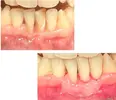

* Regenerative and mucogingival periodontal surgery (treatment of gum recessions, treatment of gummy smile)

* Treatment of gingival enlargements

* Treatment of advanced periodontal diseases